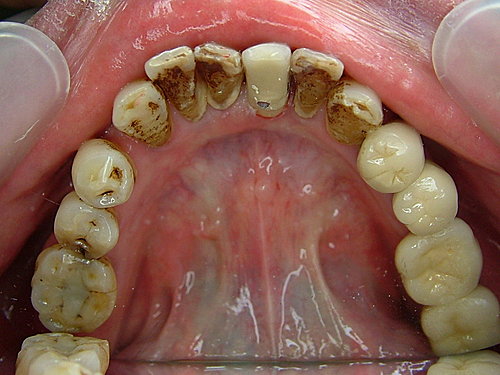

植牙手術後三個月 .... 癒合良好 .... 但牙齒刷不乾淨 牙結石多 ...

裝上假牙 大功告成 .... 拜託 !牙齒還是沒刷 看到一層厚厚的牙結石 .... 總不能天天來診所洗牙吧!

唉... 天助 人助 自助.....